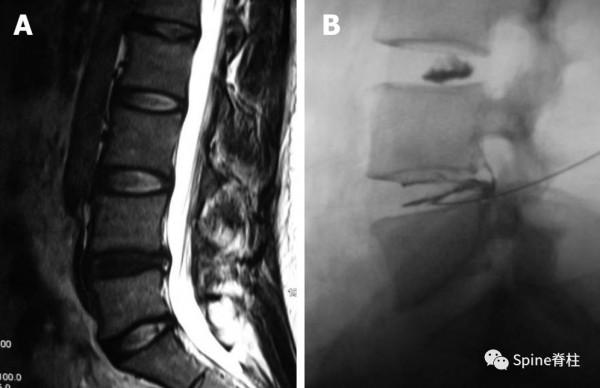

這個腰椎MRI符合上述病人的影像學結果,但很多基層醫院醫生會給予“腰椎間盤突出”的診斷,其實,最可能的診斷應該為“椎間盤源性腰痛”。

(Peng B. World J Orthop 2013; 4(2): 42-52)

椎間盤造影機制。A:椎間盤內注射的造影劑流向纖維環;B:椎間盤內注射的造影劑流向終板